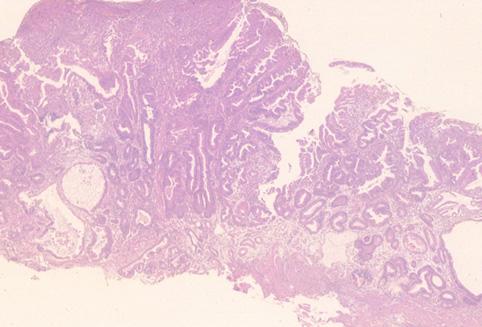

Criteria of Hist.ClassificationMalignant epithelial tumor/Adenocarcinoma

LocationStomach/Body

Technique, MethodHistology

Macroscopic TypesType 0/IIa (IIa) Superficial elevated type

Size10 - 14

Depth of Tumor Invasionmucosa